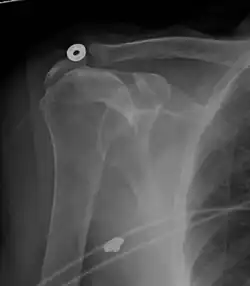

Рентгеновская проекционная рентгенография не может напрямую выявить разрывы вращающей манжеты, «мягких тканей», и, следовательно, обычные рентгеновские лучи не могут исключить повреждение манжеты. Однако косвенные доказательства патологии можно увидеть в случаях, когда одно или несколько сухожилий подверглись дегенеративной кальцификации (кальцифицирующий тендинит). Головка плечевой кости может мигрировать вверх (высоко расположенная головка плечевой кости) вследствие разрыва подостной или комбинированной надостной и подостной мышцами.[44] Миграцию можно измерить расстоянием между:

- Линией, пересекающая центр линии между верхним и нижним краями суставной поверхности суставной впадины (синяя на изображении).

- Центром наиболее подходящего круга, расположенный над суставной поверхностью плечевой кости (зеленый на изображении)

Обычно первый расположен ниже второго, и поэтому переворот указывает на разрыв вращательной манжеты.[44] Длительный контакт между высоко расположенной головкой плечевой кости и акромионом над ней может привести к обнаружению на рентгеновских снимках износа головки плечевой кости и акромиона или вторичного дегенеративного артрита плечевого сустава, называемого артропатия манжеты.[43] Случайные рентгенологические находки костных шпор в соседнем акромиально-ключичном суставе могут показать костную шпору, растущую от внешнего края ключицы вниз к вращающей манжете. На нижней стороне акромиона также можно увидеть шпоры, которые, как когда-то считали, вызывают прямое истирание вращающей манжеты из-за контактного трения, концепция, которая в настоящее время считается спорной.